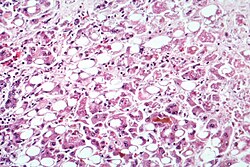

![]() Alkoqol hepatiti ilə yoluxmuş qaraciyər hüceyrəsinin mikrofotoqrafiyası | |